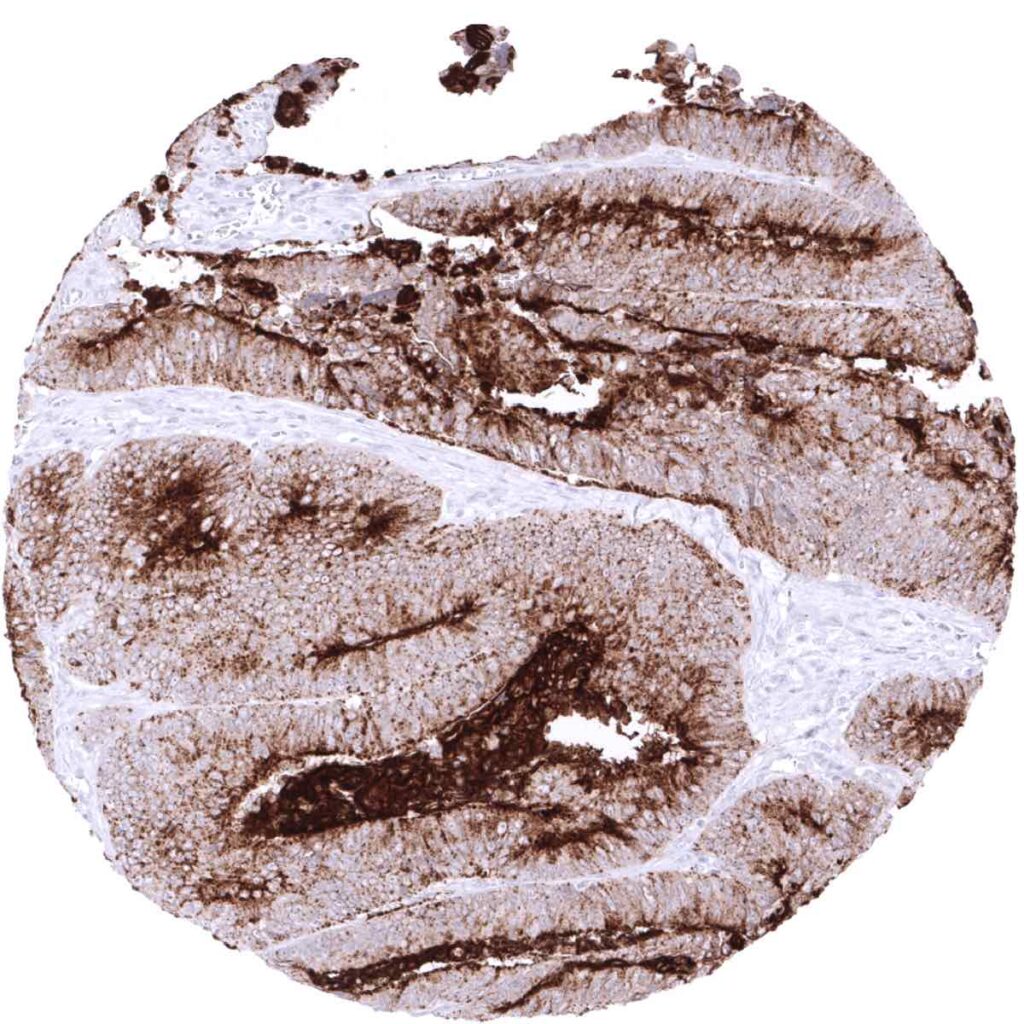

Colon- Colorectal adenocarcinoma with moderate to strong ACE2 immunostaining showing apical membrane predominance. (ACE2 immunohistochemistry)

Colon- Colorectal adenocarcinoma with strong ACE2 immunostaining, predominantly at the apical membranes. (ACE2 immunohistochemistry)